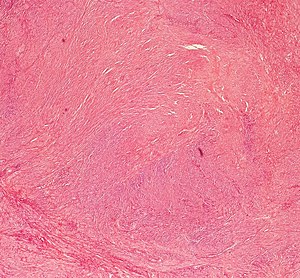

leiomyoma uterine 10x magnification leiomyomas pathology microscopyu symptoms

leiomyoma uterus pathology slide nus virtual

leiomyoma uterus pathology muscle smooth gross genital benign simple slides